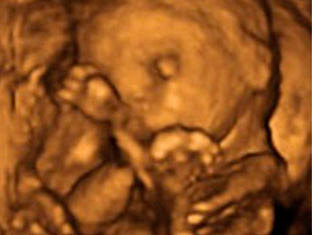

• Semana 19

19

Semana 19

-El sistema nervioso central se empieza a desarrollar rápidamente, sobre todo aquellas áreas destinadas a los sentidos del gusto, el olfato, la audición, la visión y el tacto (Algunos estudios indican que el bebé ya puede oír).

-Empiezan las etapas de sueño y de actividad.